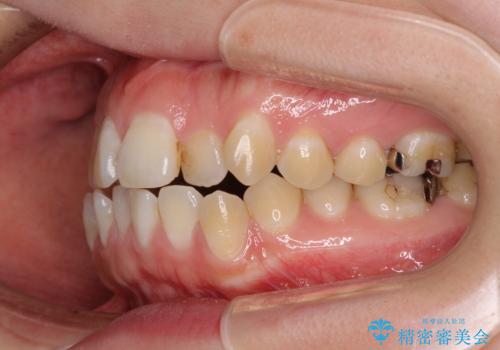

- 前歯のデコボコを気にして来院された患者様です。

前歯のデコボコはもちろん気になるところですが、舌の突出癖により上下前歯が非接触となっている状態でした。

上下前歯が非接触である開咬は、インビザラインによる治療がお勧めではありますが、しっかりと使う自信がないとのことで、ワイヤー装置にて治療を行うこととしました。

デコボコはあっという間に改善されましたが、開咬の改善に時間がかかりました。

舌の突出癖改善のトレーニングをしっかりと行っていただき、上下前歯が接触する咬み合わせを達成することができました。